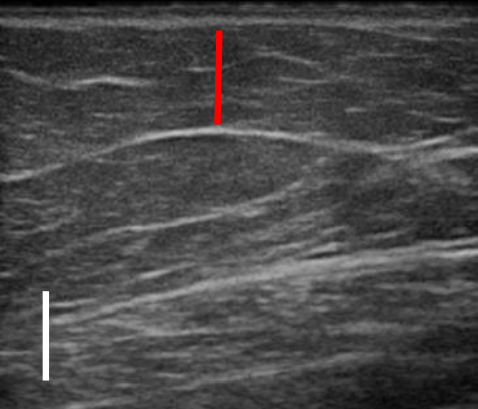

트루스컬프 아이디 시술 전, 12주 후 초음파를 비교한 사진입니다.

위 사례의 경우 지방량이 워낙 많다 보니 시술 후 겉으로 드러난 변화는 적었으나 실제로 감소한 지방량은 상당히 많았습니다.

시술 전과 비교했을 때 약 31% 정도 지방이 감소했습니다.

복부, 옆구리살이 너무 많은 경우 실제 눈에 보이는 것보다 내부에 쌓여있는 지방이 두터운 경우가 많아 시술을 해도 큰 변화를 보이지 않는 경우가 많은데요. 실제로 시술 후 큰 변화가 없어 실망하는 분들도 많지만 위와 같이 초음파 검사를 통해 속을 들여다보면 상당 부분 지방이 감소한 것을 확인할 수 있습니다.